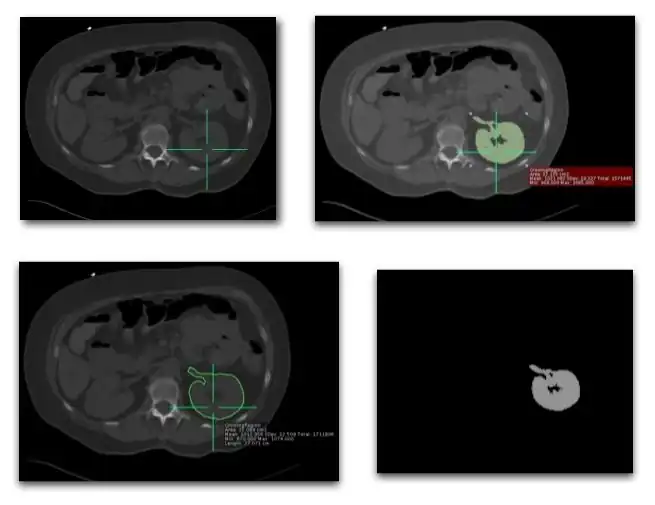

- A common technique is based on firstly defining a starting pixel in the object and then testing neighbouring pixels on the basis of a specific criterion for addition to a growing region. This criterion could be based on pixel value considerations, as in Figure 5.13.6 for instance, or on the anticipated size or shape of the object.

- Note that this approach can readily be extended to grow regions in three-dimensions when the image data consists of a set of contiguous tomographic slices.